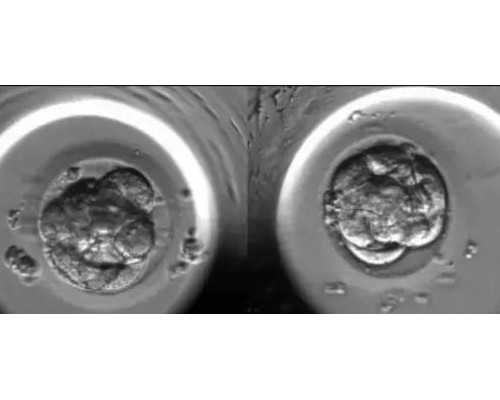

泰国做试管婴儿为什么成功率高,据供卵试管婴儿权威机构卵细胞库相关数据统计表明,供卵试管婴儿成功率与年龄无绝对关系,这也是为什么新闻报道还有六十多岁成功怀孕生子案例的原因,究其原因我们都知道影响试管婴儿成功率的两大因素是卵子质量和子宫内膜容受性,那么为什么借赠卵做供卵试管婴儿成功率就高,因为供卵是人为选择了最优质的卵子,这样就有了优质的胚胎,所以在子宫环境合格前提下选择供卵试管婴儿就有很高的成功率保障。